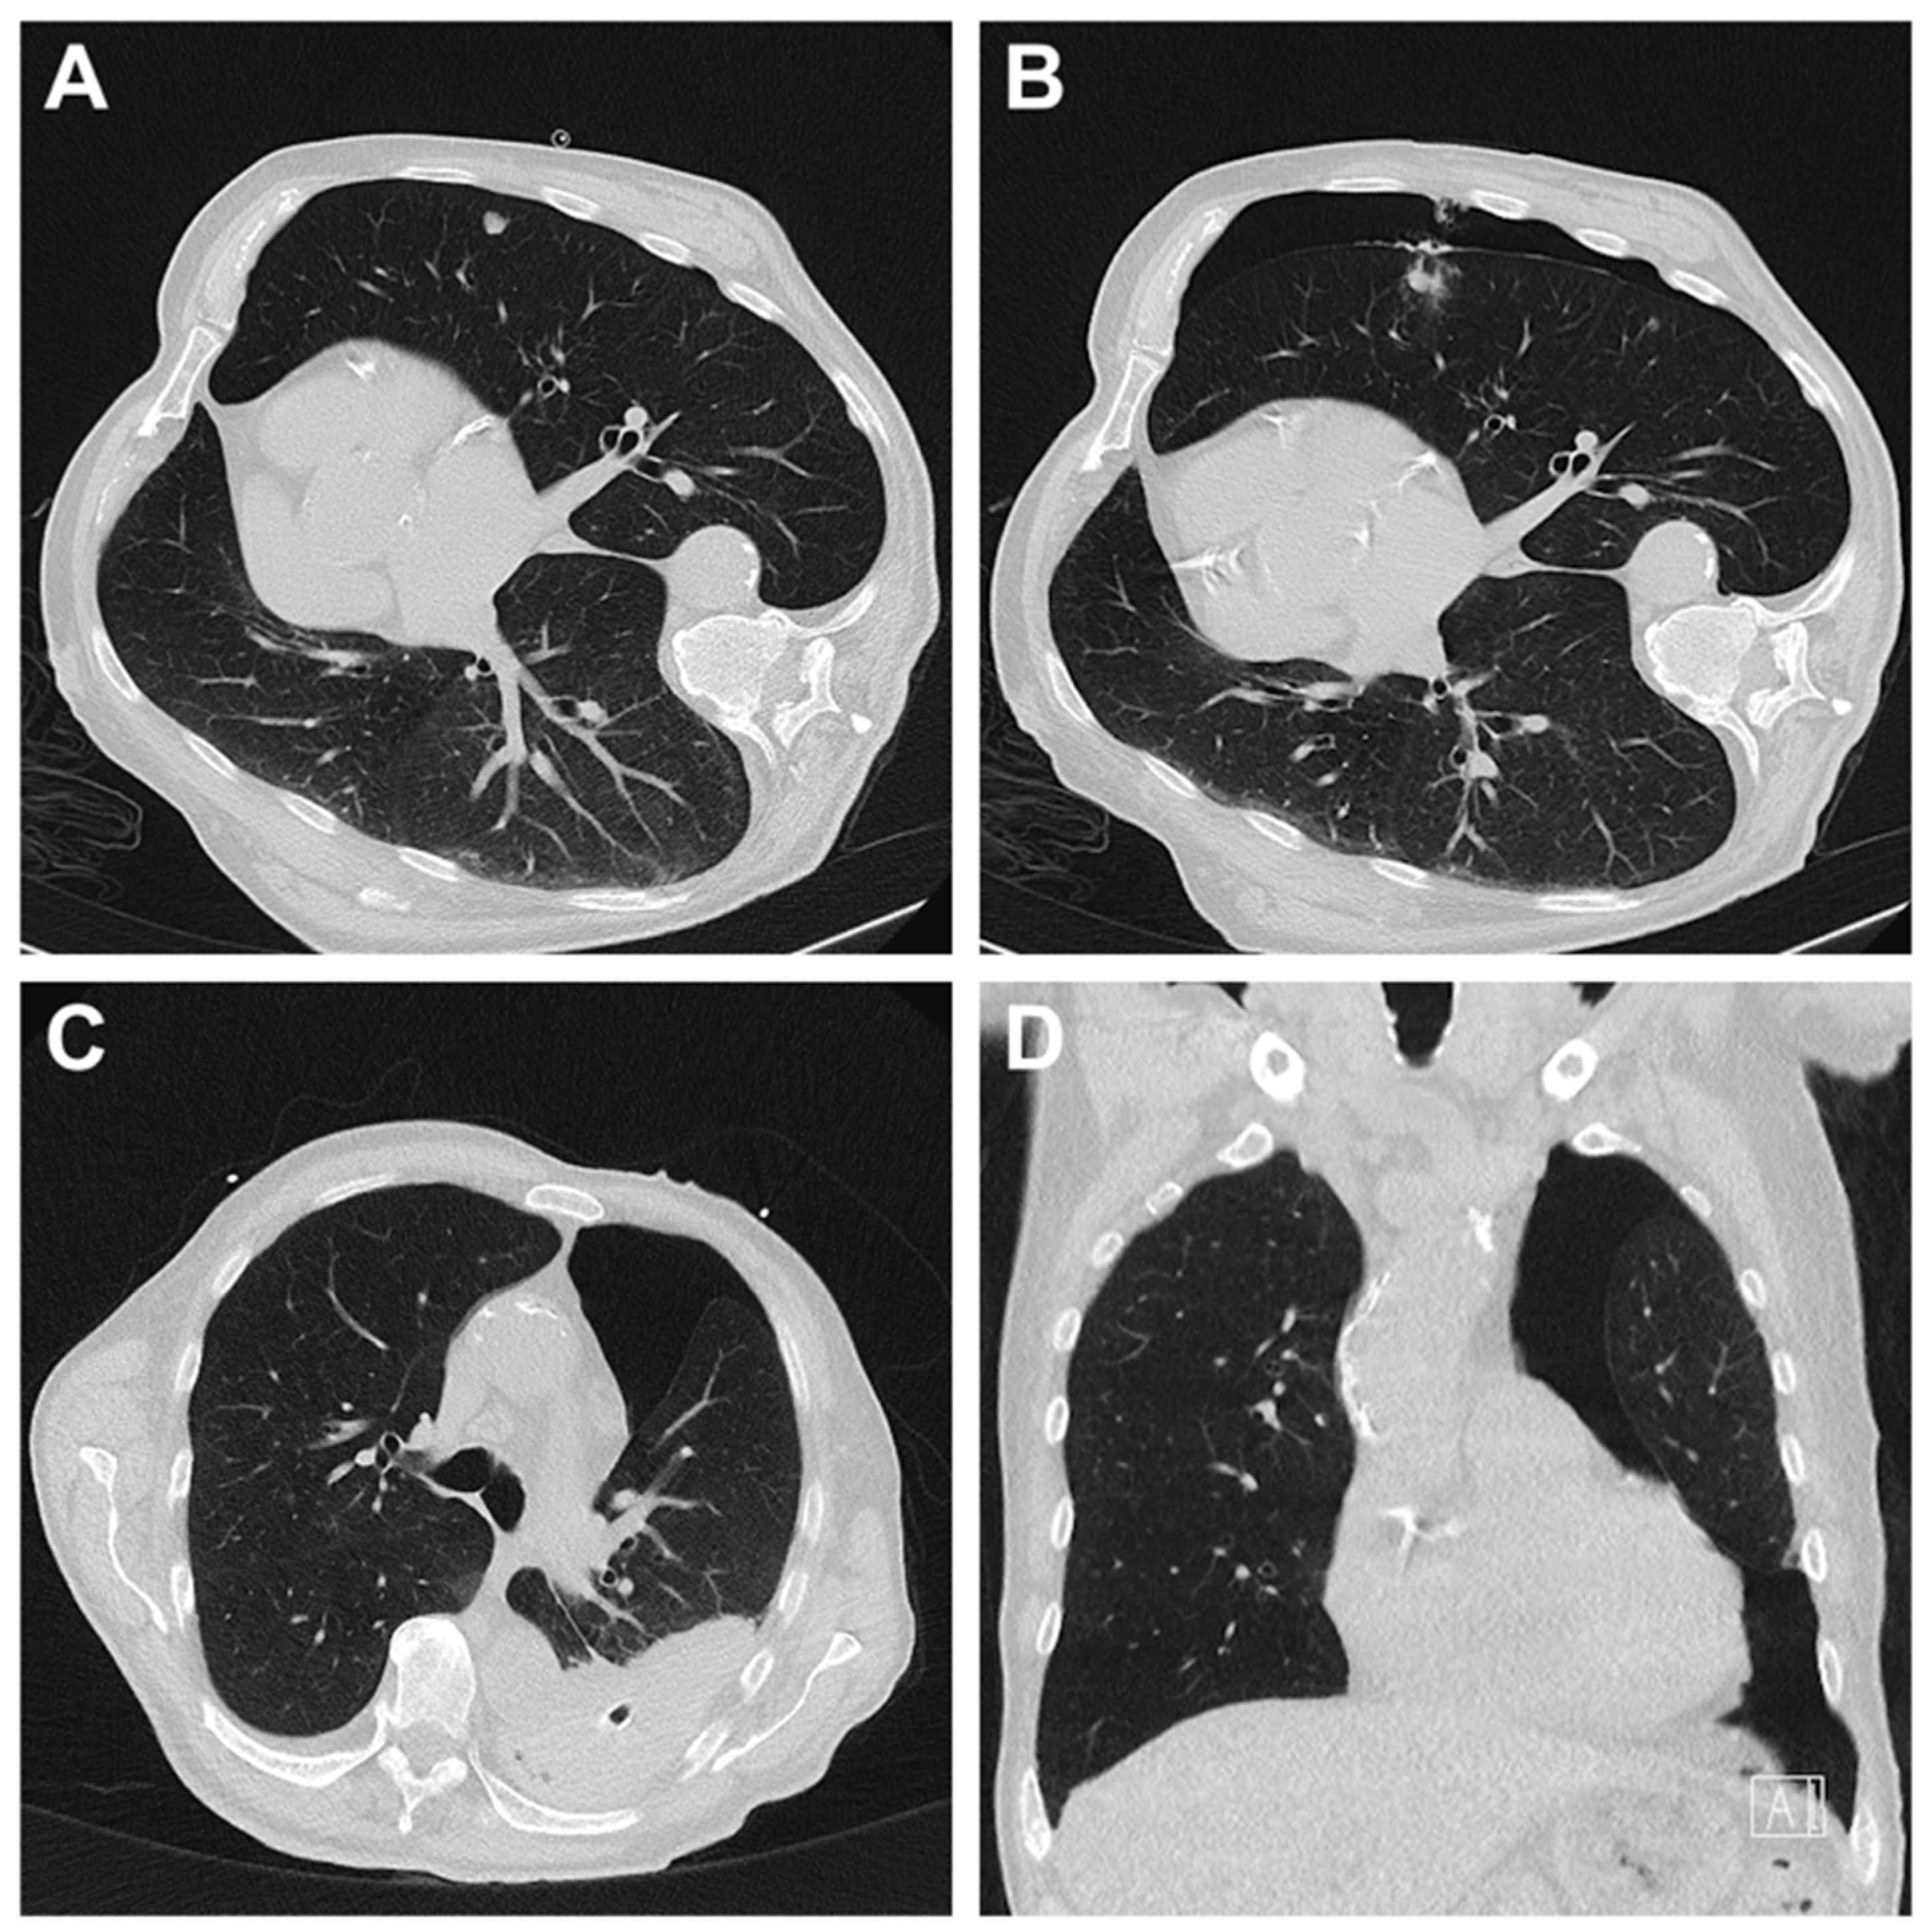

3.3. Radiation Dose for CT-Guided Biopsies